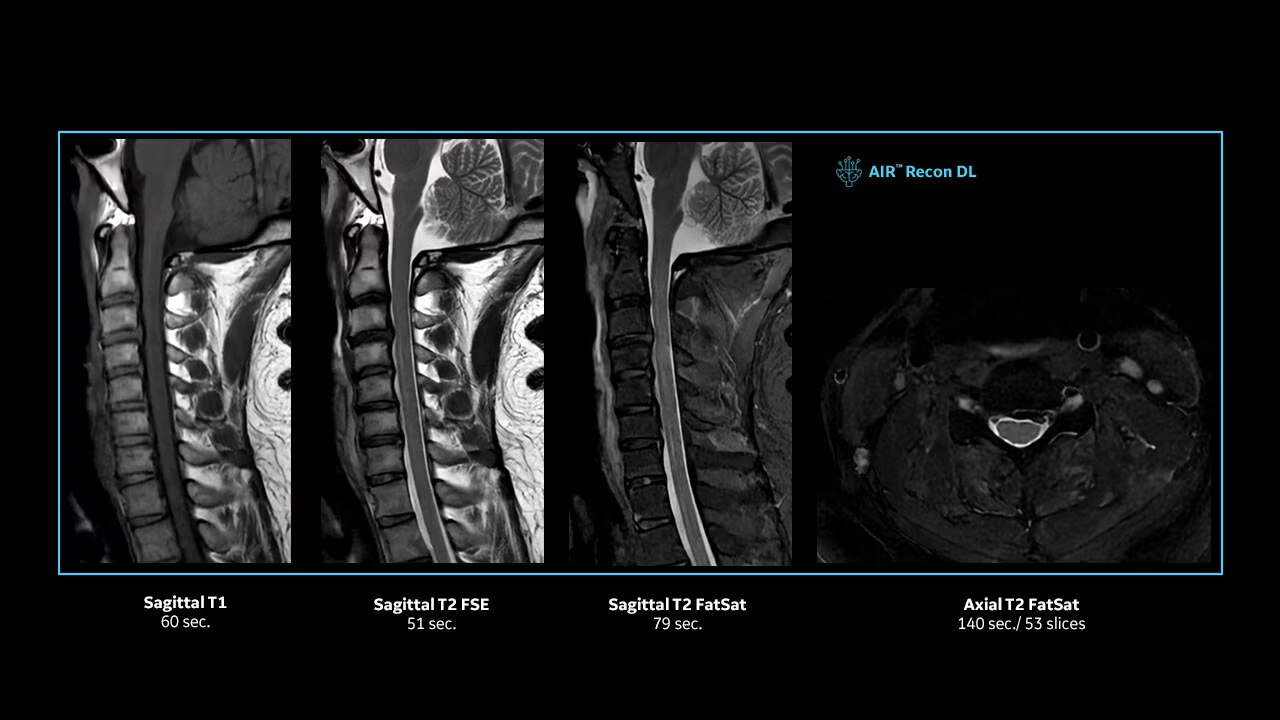

Achieve pin-sharp image quality with pioneering AIR™ Recon DL AI technology.

With access to the latest advanced AI technology, you can scan all anatomies and achieve pin-sharp images. Our pioneering deep learning-based reconstruction algorithm AIR Recon DL accelerates scan time and puts patients at ease.